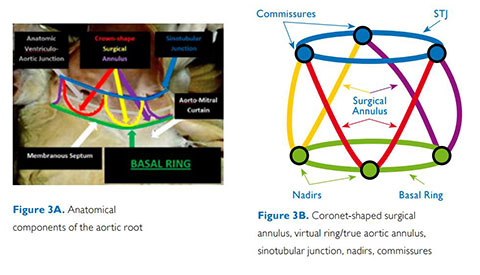

تم تشخيص أحد المرضى لديك بتضيّق في الصمام الأورطي المصحوب بأعراض. يبلغ عمر المريضة 85 عامًا وهي تعاني من السكري وارتفاع ضغط الدم. أنت تدرك خطورة وضعها الصحي ما يجعلها غير مناسبة لجراحة القلب ولكن يسمح لها بأن تكون مرشحة لاستبدال الصمام الأورطي باستخدام القسطرة (TAVR). في يومنا هذا، تمنح حلول التصوير المبتكرة والأجهزة التي تعمل عن طريق الجلد الأمل لبعض المرضى الذين لا تتوفر لهم حتى الآن أي خيارات علاجية أخرى.